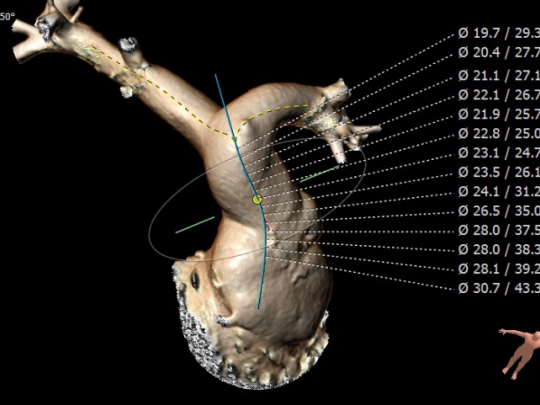

CT重建肺动脉

主肺动脉腰部截面